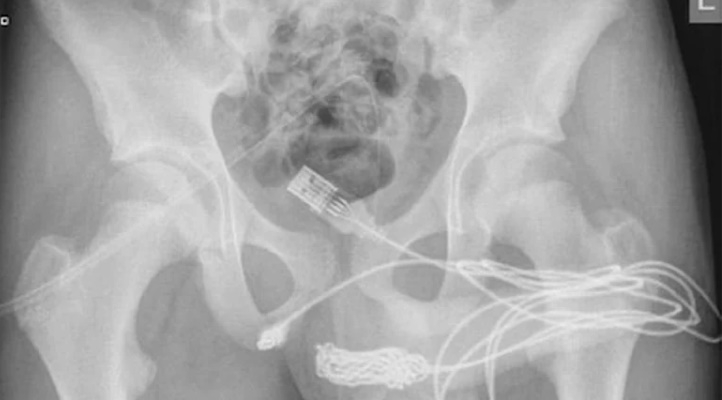

Yaşadığı olayı kaldırıldığı hastanede doktorlara anlatan gencin röntgen sonucunu inceleyen bilim insanları ise şaşkına döndü. “Cinsel deney” uğruna sağlığını riske atan gencin penisinden USB kablo zorlukla çıkarıldı.

Ameliyatı gerçekleştiren doktorlar durumu kamuoyuna hazırladıkları bir rapor ile duyururken, USB kablolarının vücut içinde düğüm olduğunu ve bu sebeple ameliyatın büyük bir zorluk içerisinde gerçekleştiğini açıkladı.

Science Direct isimli medya platformunun Urology isimli bilimsel dergiden hazırladığı haberde yer alan bilimsel araştırmada olayın 2021’de meydana geldiği belirtildi. Doktorların kaleme aldığı bilimsel araştırmada, “Vücuda yerleştirilen cisim derin doku üzerinden çıkarıldı. Kablolar penis ucundan çıkarıldı” denilirken ismi açıklanmayan gencin cinsel deney için bunu yaptığı ve herhangi bir zihinsel rahatsızlığı olmadığı da duyuruldu.